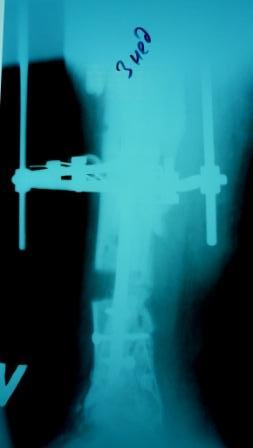

2)  После репозиции более очевидна стала проблема дефекта кости в верхней трети голени, два фрагмента свободно лежат. Остановились на варианте перехода на интрамедуллярный синтез стержнем с покрытием костный цемент+ванкомимцин и замещении дефекта с помощью транспорта фрагмента (рис 2)

Имя     : Рис 2 после операции 27.02.09.JPG

Тип     : image/jpeg

Размер  : 14504 байтов

Описание: отсутствует

Url     : http://weborto.net:8080/pipermail/ortho/attachments/20090405/a3dc024e/attachment-0013.jpeg

Имя     : Рис 2 после операции 27.02.09 (1).JPG

Размер  : 14471 байтов

Url     : http://weborto.net:8080/pipermail/ortho/attachments/20090405/a3dc024e/attachment-0014.jpeg